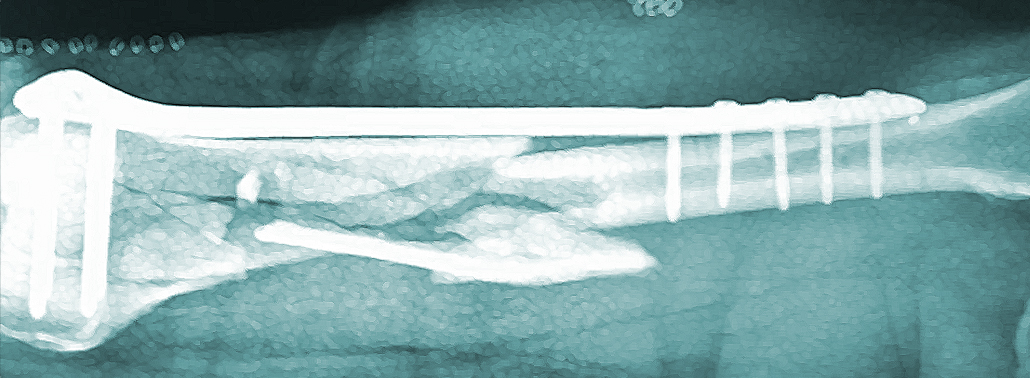

Son dispositivos empleados en la estabilización ósea y que se basan en placas dotadas de orificios a través de las que se colocan tornillos que se fijan al hueso. En los últimos años, también existe la posibilidad de complementar la sujeción por medio de cables o bandas.

Las placas han ido evolucionando en su diseño y, actualmente, están fabricadas con formatos específicos para adaptarse a las distintas localizaciones anatómicas. Además, los tornillos pueden enroscarse a la placa, formando lo que se conoce como construcciones de ángulo estable e incrementando las indicaciones del implante.

Hay que tener presente que las fracturas articulares tienen una serie de peculiaridades. El hueso de esas regiones es de tipo esponjoso, la fragmentación suele ser elevada y es muy importante restaurar correctamente la línea articular. Es por ello que el uso de placas que se adapten a la anatomía de la región y que permitan fijar el hueso evitando el colapso.